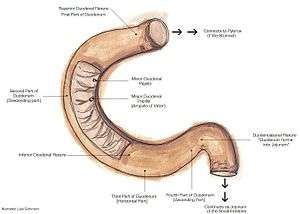

Food starts to arrive in the small intestine one hour after it is eaten, and after two hours the stomach has emptied. Until this time the food is termed a bolus. It then becomes the partially digested semi-liquid termed chyme.

In the small intestine, the pH becomes crucial; it needs to be finely balanced in order to activate digestive enzymes. The chyme is very acidic, with a low pH, having been released from the stomach and needs to be made much more alkaline. This is achieved in the duodenum by the addition of bile from the gall bladder combined with the bicarbonate secretions from the pancreatic duct and also from secretions of bicarbonate-rich mucus from duodenal glands known as Brunner's glands. The chyme arrives in the intestines having been released from the stomach through the opening of the pyloric sphincter. The resulting alkaline fluid mix neutralises the gastric acid which would damage the lining of the intestine. The mucus component lubricates the walls of the intestine.

When the digested food particles are reduced enough in size and composition, they can be absorbed by the intestinal wall and carried to the bloodstream. The first receptacle for this chyme is the duodenal bulb. From here it passes into the first of the three sections of the small intestine, the duodenum. (The next section is the jejunum and the third is the ileum). The duodenum is the first and shortest section of the small intestine. It is a hollow, jointed C-shaped tube connecting the stomach to the jejunum. It starts at the duodenal bulb and ends at the suspensory muscle of duodenum. The attachment of the suspensory muscle to the diaphragm is thought to help the passage of food by making a wider angle at its attachment.

Most food digestion takes place in the small intestine. Segmentation contractions act to mix and move the chyme more slowly in the small intestine allowing more time for absorption (and these continue in the large intestine). In the duodenum, pancreatic lipase is secreted together with a co-enzyme, colipase to further digest the fat content of the chyme. From this breakdown, smaller particles of emulsified fats called chylomicrons are produced. There are also digestive cells called enterocytes lining the intestines (the majority being in the small intestine). They are unusual cells in that they have villi on their surface which in turn have innumerable microvilli on their surface. All these villi make for a greater surface area, not only for the absorption of chyme but also for its further digestion by large numbers of digestive enzymes present on the microvilli.

The chylomicrons are small enough to pass through the enterocyte villi and into their lymph capillaries called lacteals. A milky fluid called chyle, consisting mainly of the emulsified fats of the chylomicrons, results from the absorbed mix with the lymph in the lacteals. Chyle is then transported through the lymphatic system to the rest of the body.

The suspensory muscle marks the end of the duodenum and the division between the upper gastrointestinal tract and the lower GI tract. The digestive tract continues as the jejunum which continues as the ileum. The jejunum, the midsection of the small intestine contains circular folds, flaps of doubled mucosal membrane which partially encircle and sometimes completely encircle the lumen of the intestine. These folds together with villi serve to increase the surface area of the jejunum enabling an increased absorption of digested sugars, amino acids and fatty acids into the bloodstream. The circular folds also slow the passage of food giving more time for nutrients to be absorbed.

The last part of the small intestine is the ileum. This also contains villi and vitamin B12; bile acids and any residue nutrients are absorbed here. When the chyme is exhausted of its nutrients the remaining waste material changes into the semi-solids called feces, which pass to the large intestine, where bacteria in the gut flora further break down residual proteins and starches.[30]